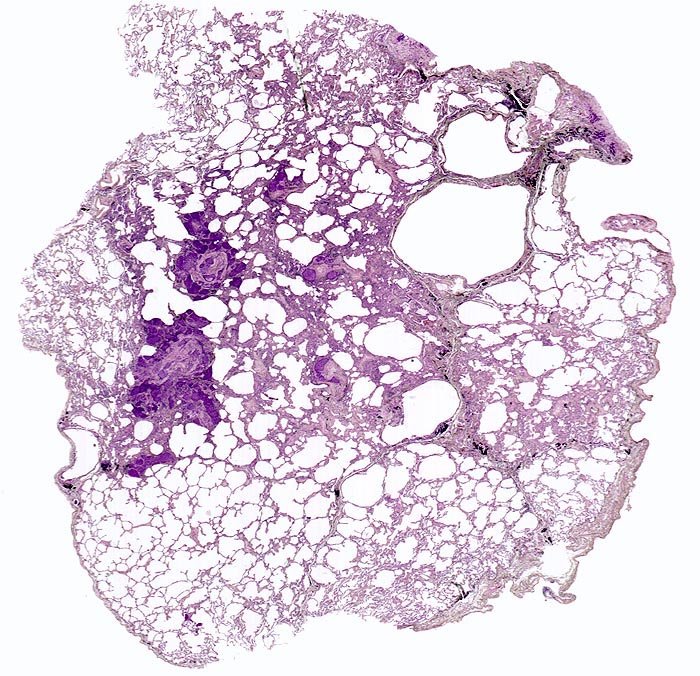

Lymphangiosis carcinomatosa, zentroazinäres Lungenemphysem

In der Übersicht sind mehrere Tumorherde erkennbar sowie eine Destruktion des Lungenparenchyms im Bereich der mit Anthrakosepigment schwarz angefärbten Azinuszentren (zentroazinäres Emphysem).

Metastasierendes Tumorleiden bei unbekanntem Primärtumor. Autoptisch primäres peripheres neuroendokrines Karzinom der Lunge mit ausgedehnter lymphogener und hämatogener Metastasierung.